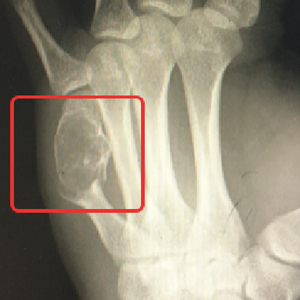

”这可不是一般的键盘手,你左手这根骨头里的东西,其实是内生性软骨瘤,它把你正常的骨头都‘融’成‘豆腐渣’了,所以骨头才会一碰就裂开,需要刮除肿瘤组织同时固定骨折的掌骨。”  杭州市第三人民医院骨科马伟副主任医师指着X片对黄先生解释道。